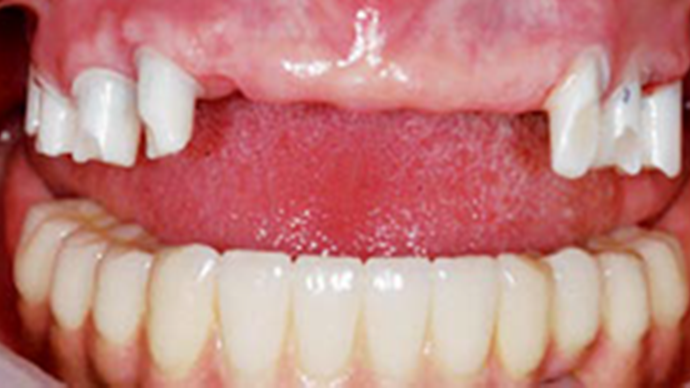

Clinical case: A Full transition from natural teeth to all-on-6 bridges

with AnyRidge implants

- Courtesy of Dr. Rabih Abi Nader, UAE -

Keywords

Full-mouth rehabilitation, minimal layering, Zirconia, all-on-6, life changing result, edentulous ,Dr. Rabih Abi Nader, AnyRidge

Products:

AnyRidge implant system

“AnyRidge shows excellent esthetic results

with Zirconia prosthesis in full-mouth rehabilitation case . ”